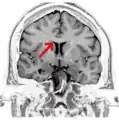

Corpus callosum

Coronal T2 (grey scale inverted) MRI of the brain at the level of the caudate nuclei emphasizing corpus callosum- Tractography of Corpus callosum